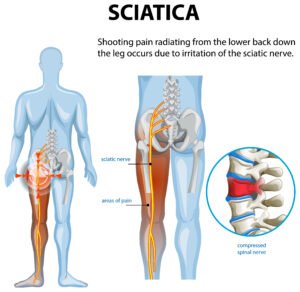

- Neck and Back Pain

- Sciatica